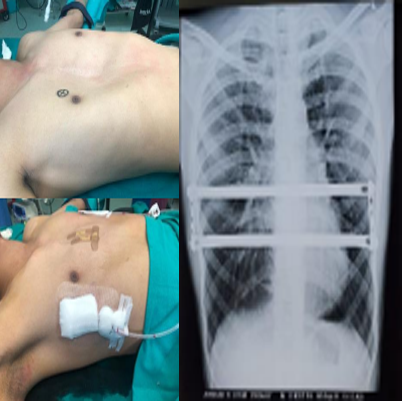

Conventionally, the surgeries at the best hospital for thoracic surgery in India were carried out through open procedures, needing major incisions and long recovery periods. The commencement of minimally invasive methods, including Video Assisted Thoracic Surgery (VATS), marked a substantial development. Nonetheless, introduction of robotics based thoracic surgery has further extended the boundaries, providing improved accuracy and control.